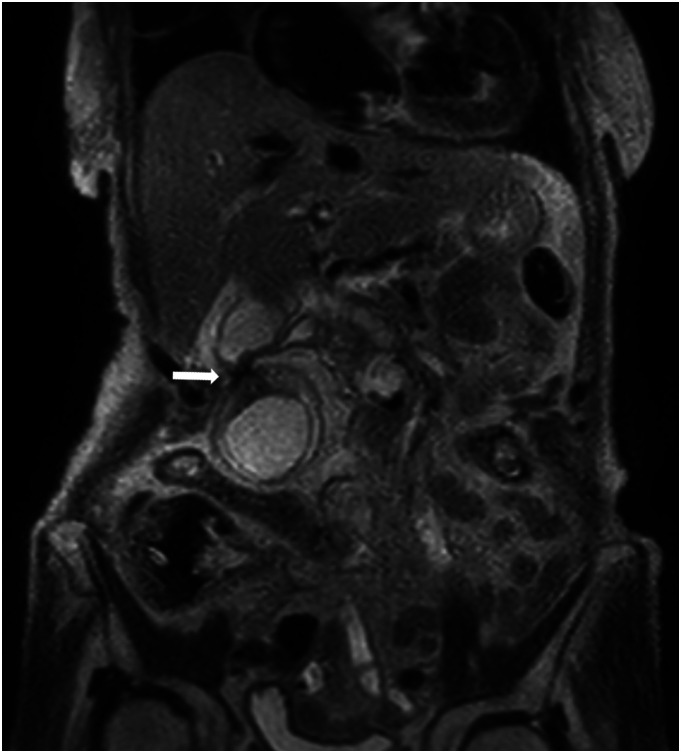

Cholecystitis is a common disease, but the occurrence of gallbladder strangulation is extremely rare. Here, we report a case of an 88-year-old woman with strangulated cholecystitis caused by an intraperitoneal band. Computed tomography (CT) scan revealed a constriction of the gallbladder body and marked wall thickening at the fundus. Additionally, the finding suggested torsion at the constricted area, which we diagnosed as gallbladder torsion. Cholecystectomy was performed immediately, and the diagnosis was strangulated cholecystitis caused by a band. The imaging findings of strangulated cholecystitis are similar to gallbladder torsion, making it difficult to diagnose preoperatively. We will discuss the imaging findings of strangulated cholecystitis and gallbladder torsion.